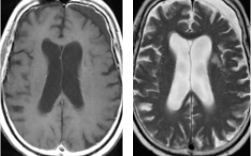

肺癌による左側頭葉転移性脳腫瘍に対してEGFR変異陽性の結果を踏まえて イレッサ(ゲファチニブ)の単独投与のみで治療したところ、腫瘍が著明に縮小しました。その後再発なく経過しています。

卵巣癌による右前頭葉を中心に多発転移性脳腫瘍に対して放射線治療単独(全脳照射)のみで腫瘍が著明に縮小しました。その後再発なく経過しています。